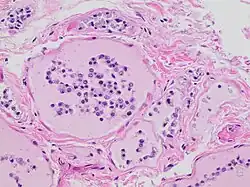

Autolysis is uncommon in living adult organisms and usually occurs in necrotic tissue as enzymes act on components of the cell that would not normally serve as substrates. These enzymes are released due to the cessation of active processes in the cell that provide substrates in healthy, living tissue; autolysis in itself is not an active process. In other words, though autolysis resembles the active process of digestion of nutrients by live cells, the dead cells are not actively digesting themselves as is often claimed, and as the synonym self-digestion suggests. Failure of respiration and subsequent failure of oxidative phosphorylation is the trigger of the autolytic process.[1] The reduced availability and subsequent absence of high-energy molecules that are required to maintain the integrity of the cell and maintain homeostasis causes significant changes in the biochemical operation of the cell.

Lysosomes are membrane-bound organelles that typically contain a broad spectrum of enzymes capable of hydrolytic deconstruction of polysaccharides, proteins, nucleic acids, lipids, phosphoric acyl esters, and sulfates. This process requires compartmentalization and segregation of enzymes and substrates via a single intracellular membrane that prevents unwarranted destruction of other intracellular components. Under normal conditions, the molecular machinery of the cell is further protected from lysosomal enzyme activity by regulation of cytosolic pH. The activity of lysosomal hydrolases is optimal at a moderately acidic pH of 5, which is significantly more acidic than the more basic average pH of 7.2 in the surrounding cytosol.[1] However, the accumulation of products of glycolysis decreases the pH of the cell, reducing this protective effect. Furthermore, lysosomal membranes damaged by water retention in the cell will release lysosomal enzymes into the cytosol. These enzymes are likely to be active due to the decreased cytosolic pH and are thus free to utilize cellular components as substrates.[1]